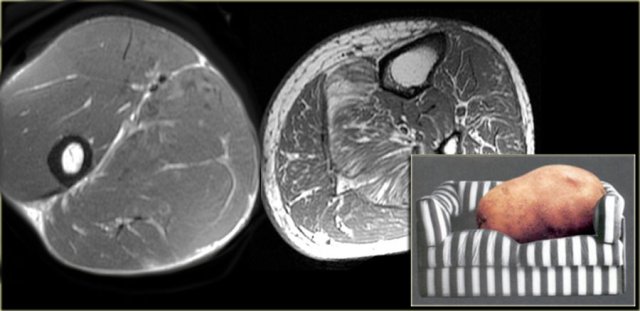

Muscle Atrophy

The fat present in a muscle will be either intramuscular or intermuscular.

There obviously is a wide range of amount of fat present.

Far left an example of an olympic gymnast with 6% body fat.

Next to it an example of most of us mortals, the so called couch potato, with much more intra- and inter-muscular fat.